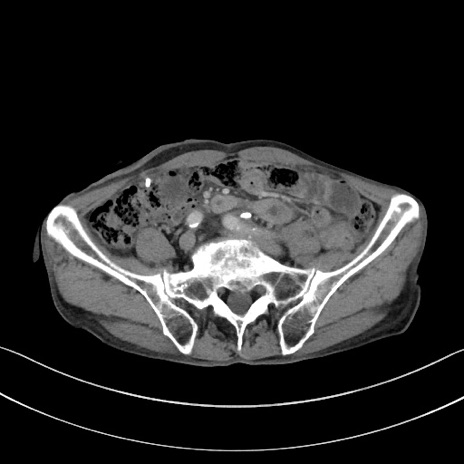

症例3(横断像)

【症例】 70歳代男性

【主訴】右鼠径部腫瘤、疼痛

【現病歴】本日朝より上記主訴あり、受診。

【既往歴】膀胱癌にて膀胱全摘、両側尿管皮膚瘻

【データ】WBC 5600、CRP 0.56